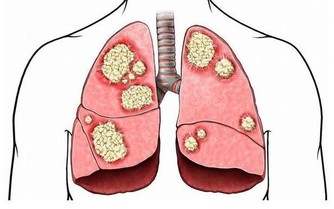

5 強壯機體、防癌抗癌萵苣含有多種維生素和礦物質,具有調節神經系統功能的作用,

其所含有機化含物中富含人體可吸收的鐵元素,對有缺鐵性貧血病人十分有利。

萵苣的熱水提取物對某些癌細胞有很高的抑制率,故又可用來防癌抗癌。